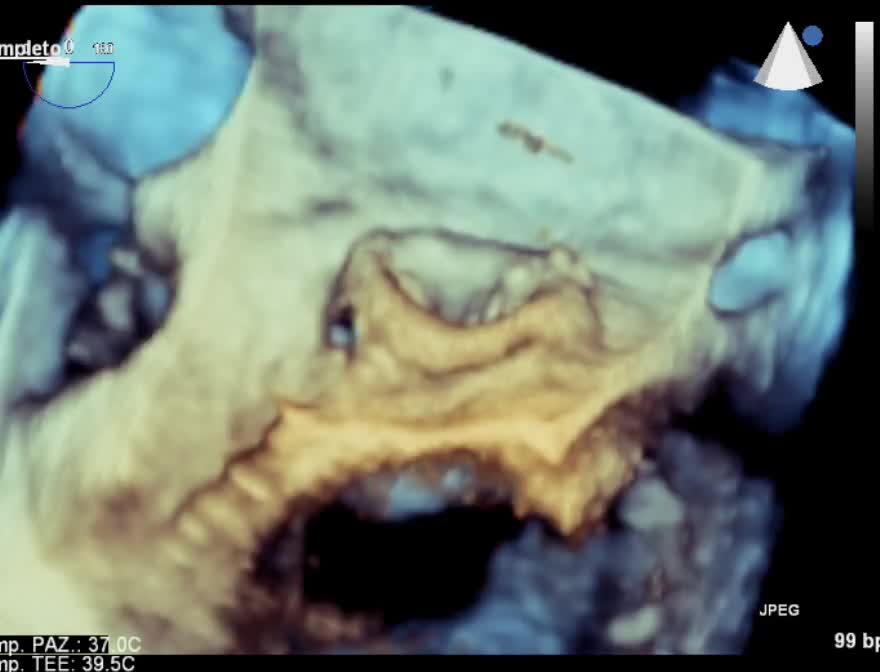

La TAVI “valve in valve”.

Categoria: Relazioni storiche Parole chiave: Area Cardio-Interventistica complicazione malfunzionamento mismatch protesi tavi valve in valve

Autore: Federico De Marco

Anno: 2021